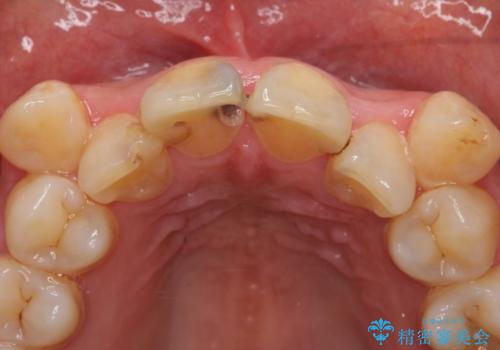

右上2は歯の神経が死んでおり、根尖病変を認めたため根管治療を行いました。

その後右上1,2番目及び左上1番目の歯に対してオールセラミッククラウンによる補綴を行いました。